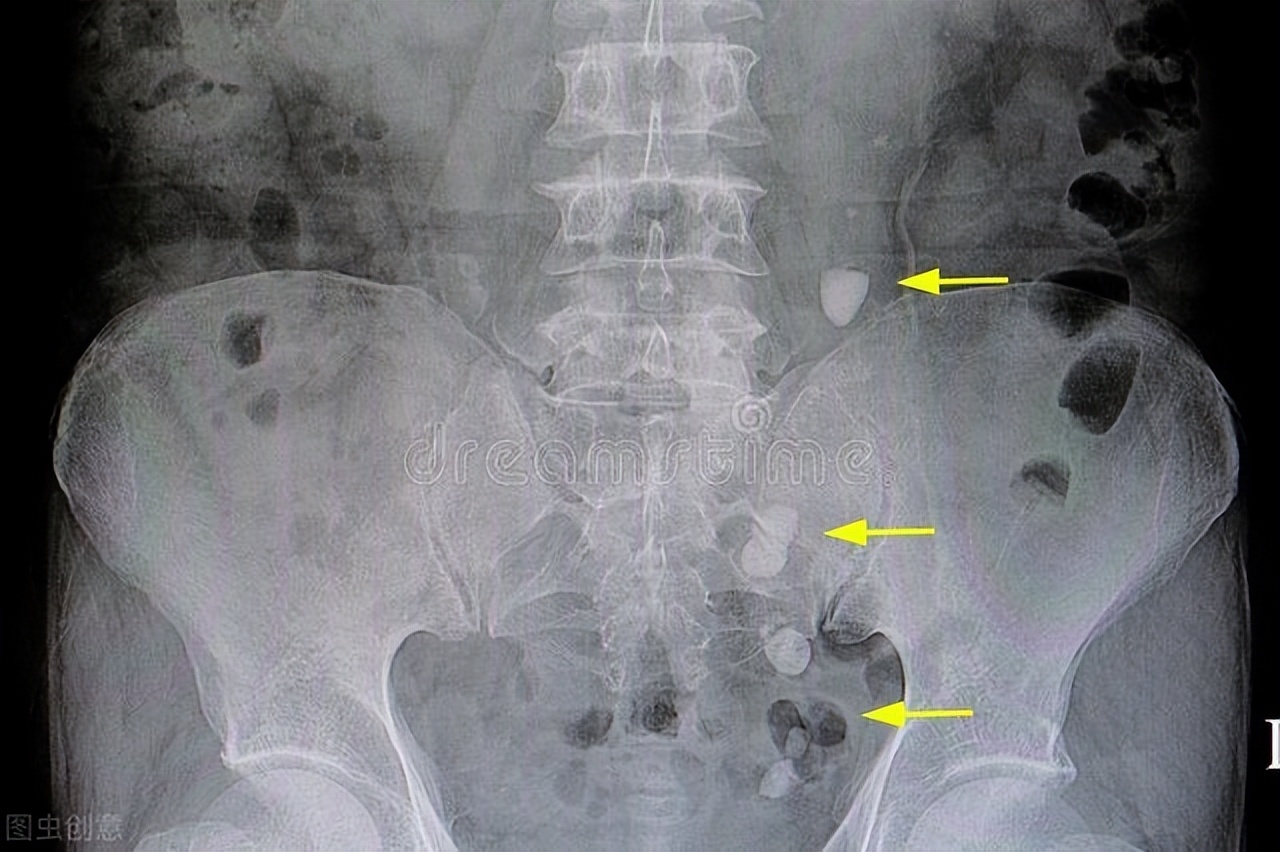

4. 肾盂肾炎或肾结石

膀胱内储存的尿液过多,压力升高,可能会导致尿液逆流回输尿管和肾盂,容易引发肾盂肾炎;尿液中的草酸钙等物质沉淀,也有形成结石的可能